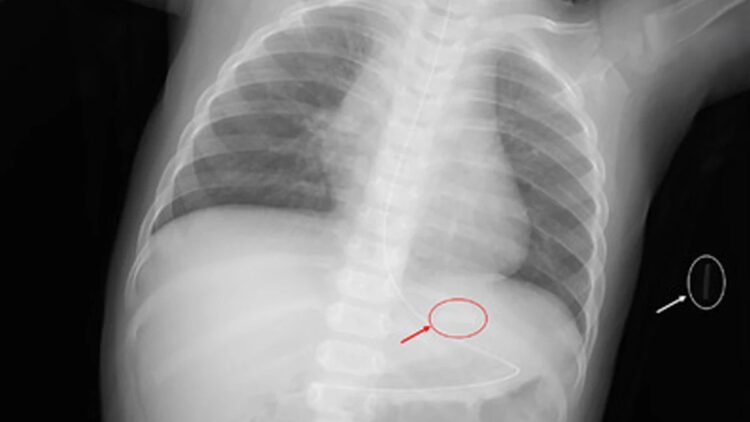

加熱菸合法販售的日本也同樣出現類似案例,福岡大學築紫醫院記錄了一名10個月大女童因誤食母親的加熱菸彈而送醫的案例。醫護人員緊急為女童進行洗胃,X光檢查顯示胃內有一個長12毫米、寬3毫米的矩形異物,取出後證實為加熱菸彈內的金屬刀片。該女童在誤食不到一小時後即出現尼古丁中毒症狀。